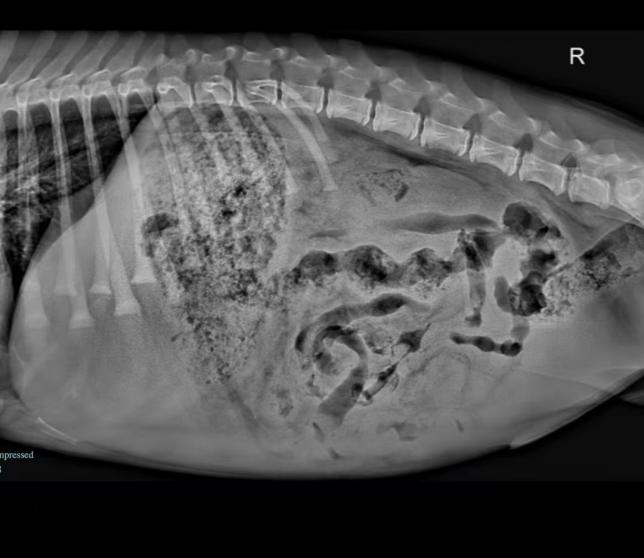

X-ray: Showed considerable abdominal fluid accumulation, suggesting an internal issue.

Ultrasound: Confirmed the presence of abdominal fluid and revealed an intussusception in the intestine. The final diagnosis was a foreign body in the digestive tract, causing intussusception and secondary bacterial peritonitis.